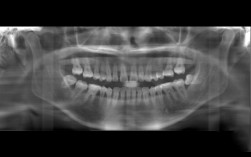

(图片来源网络,侵删) -